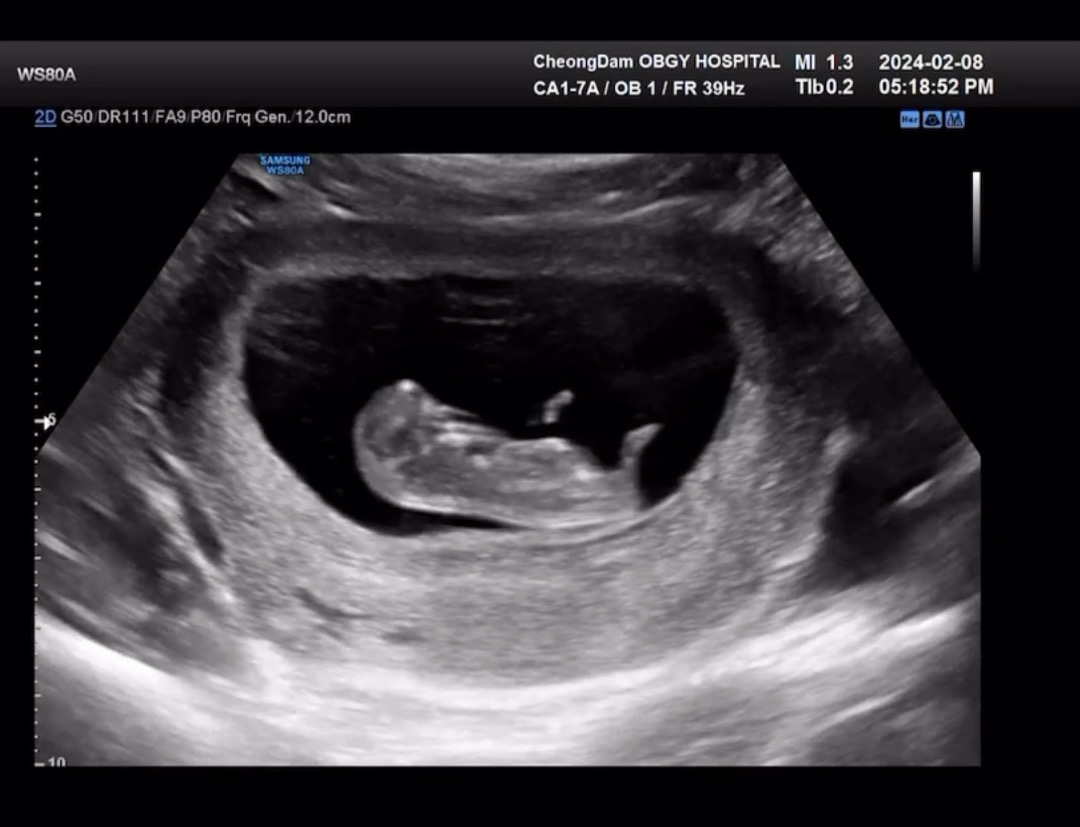

10주차 초음파 보고 왔어욥

신나게 팔다리를 파닥거리고 있어서 너무 귀여웠어욥..🥹 언제 이렇게 큰거지